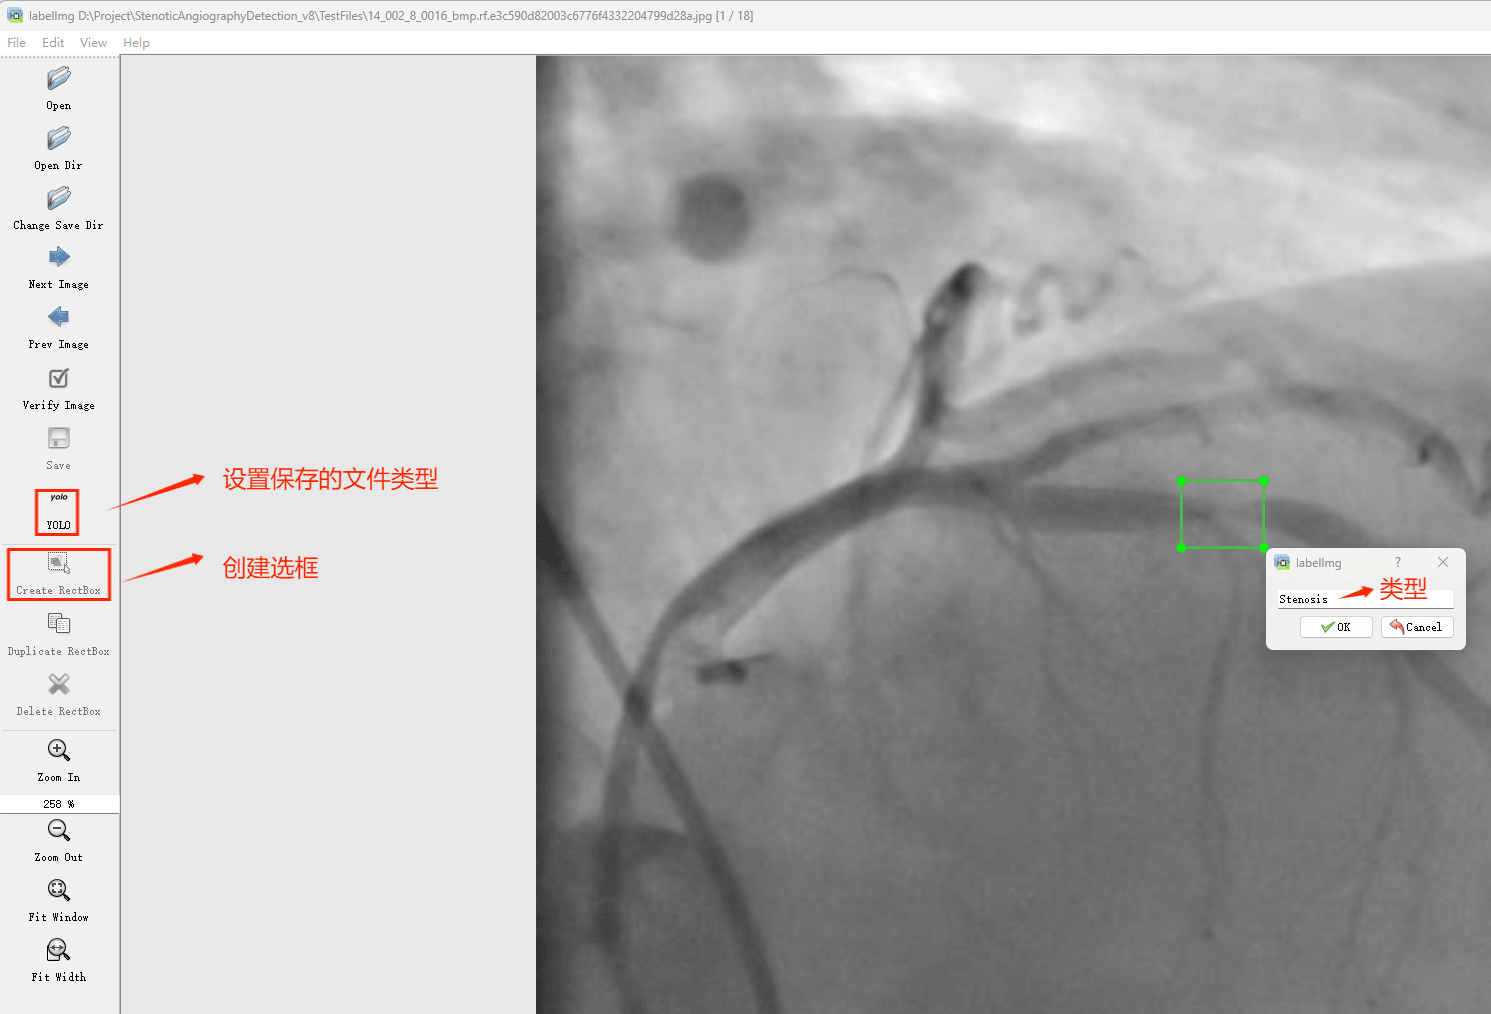

初识labelimg

打开后,我们自己设置一下

在View中勾选Auto Save mode

接下来我们打开需要标注的图片文件夹

并设置标注文件保存的目录(上图中的Change Save Dir)

接下来就开始标注,画框,标记目标的label,然后d切换到下一张继续标注,不断重复重复。